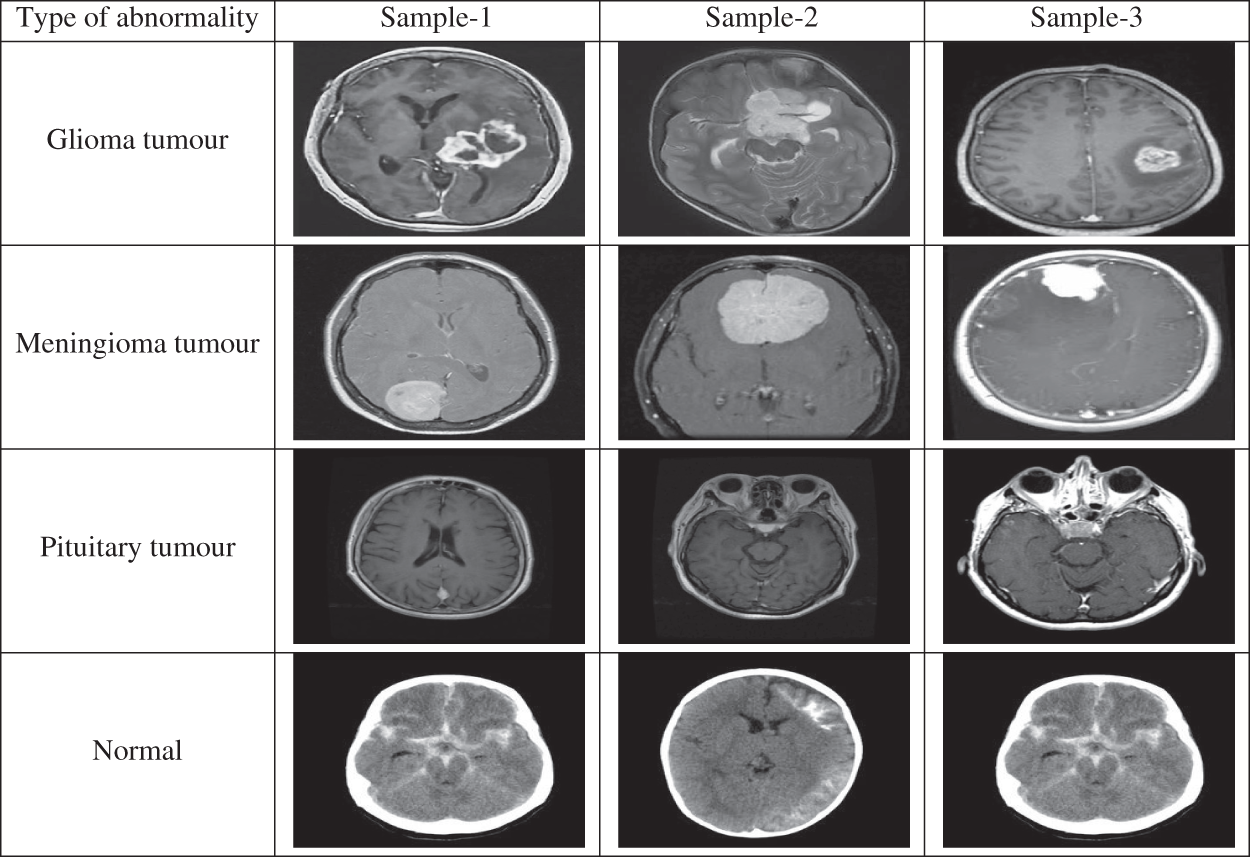

The performances of the proposed MCC system for classifying MRI brain images are assessed using a public database. It is freely downloadable from [26]. The MRI images in this database are collected from healthy and cancer affected patients and having four classes of images such as normal, glioma, meningioma and pituitary. Tab. 2 shows the class distribution of MRI brain images in this database. Fig. 5 shows sample images in each category.

Figure 5: MRI brain images in the database